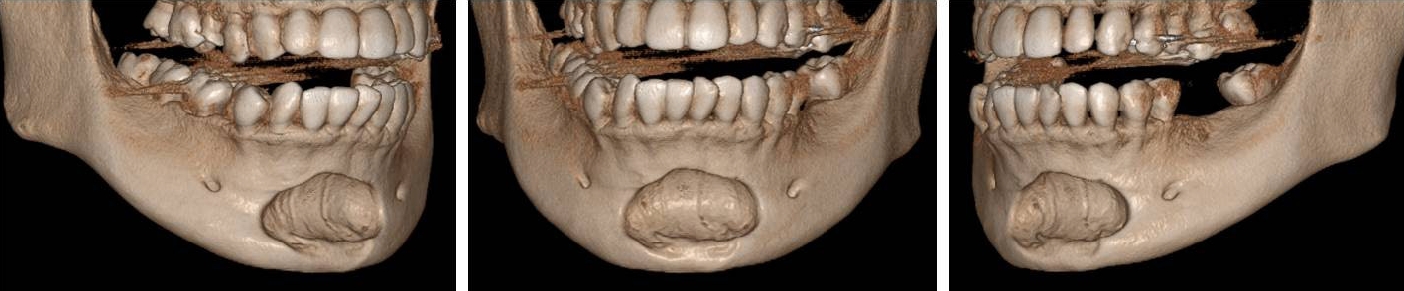

32세 여성 환자의 파노라마방사선영상에서 하악 전치부 낭이 관찰되어, 정확한 진단을 위하여 본원에 의뢰되었다. 특별한 임상증상은 없었다. 파노라마방사선영상에서 하악 우측 제1소구치에서 좌측 제1소구치 치근하방에 경계가 명확하고 피질골성 변연을 가진 타원형의 방사선투과상이 관찰되었다(Fig. 1). 방사선투과상은 해당치아들과는 무관하여 치근단낭이 배제되었고, 단순골낭의 가능성을 염두에 두고 콘빔CT 검사를 시행하였다. 콘빔CT에서 중심성 골내 병소가 아닌 악골의 순측에서 설측으로 함몰된 변연성 병소가 관찰되었다(Fig. 2). 병소의 경계는 매우 평활하였고, 단면상에서는 넓은 접시모양처럼(Fig. 3), 악골 절단면상에서는 반달모양처럼 함몰되어 있었다(Fig. 4). 설측 피질골은 비박되어 있었으나 천공은 관찰되지 않았다. 함몰된 부위는 공기가 아닌 연조직의 방사선투과상으로 채워졌으나, 콘빔CT에서는 대조도가 낮아서 연조직간의 감별이 가능하지 않았다(Fig. 5). 관찰된 턱 끝 부위의 골 함몰이 해부학적 변이인지 아닌지를 감별하기 위하여 환자의 과거 병력을 알아보았다. 환자는 2년 전에 턱 끝 부위에 미용 필러 시술을 받았다고 하였다. 방사선영상소견과 문진결과를 토대로, 미용 필러와 관련된 골흡수를 의심하였다. 이후 외과적으로 미용 필러 제거와 함몰된 부위에 골이식이 시행되었다. 수술 중에 육안으로 남아있는 미용 필러와 작은 석회화 물질들이 확인되었다. 수술 후 생검에서 다핵거대세포와 결절석회화가 관찰되었고, 피부석회화(calcinosis cutis)가 의심된다는 결과를 받았다. 이상의 술 전 검사 및 술 후 소견을 종합하여, 파노라마방사선영상에서 관찰된 방사선투과상은 치성낭이나 해부학적 변이가 아니고 미용 필러에 의한 하악골 순측 골흡수로 최종 진단되었다.

Cone-beam computed tomographic 3-dimensional reconstruction image. A peripheral bone defect is observed extending from the labial to the lingual aspect of the mandible, rather than a centrally located intraosseous lesion.